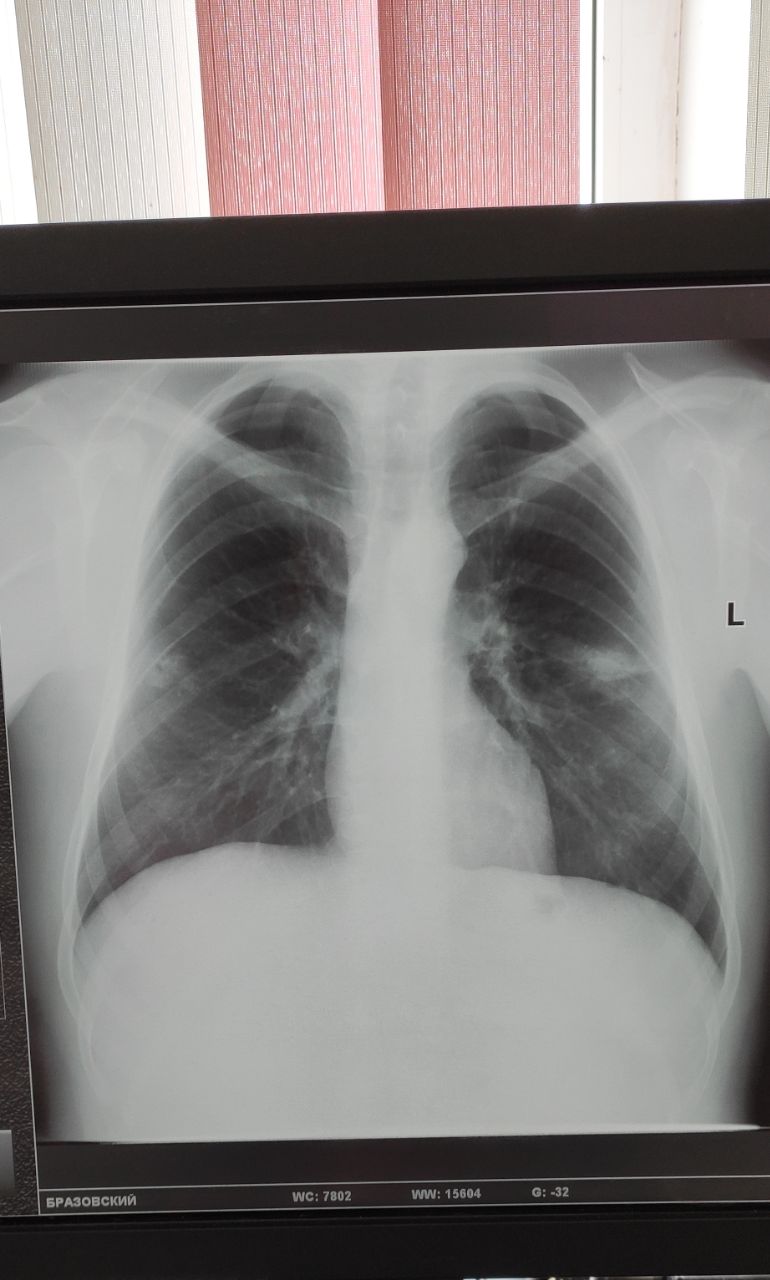

Пациент, 37 лет, жалоб не предъявляет, отправили на контроль. Злоупотребляет алкоголем. Это снимки сегодня

Маруська in Radiology/Рентгенология Чат

Это снимки в ноябре, лечили пневмонию

Нужна консультация фтизиатра? Или думать в другом направлении?

Вообще без динамики. А ранее любые есть снимки?

Снимки есть, но я не сфоткала. Там этих теней не было

Процесс активный значит

Можно предположить что мои или бои, но не характерное расположение

Диаскин, пцр, кт и мокроту

Значит фтизиатр однозначно и кровь на вич

То что алкоголь в анамнезе уже звоночек